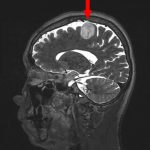

No.’25_88 手術前1

No.’25_88 手術前2